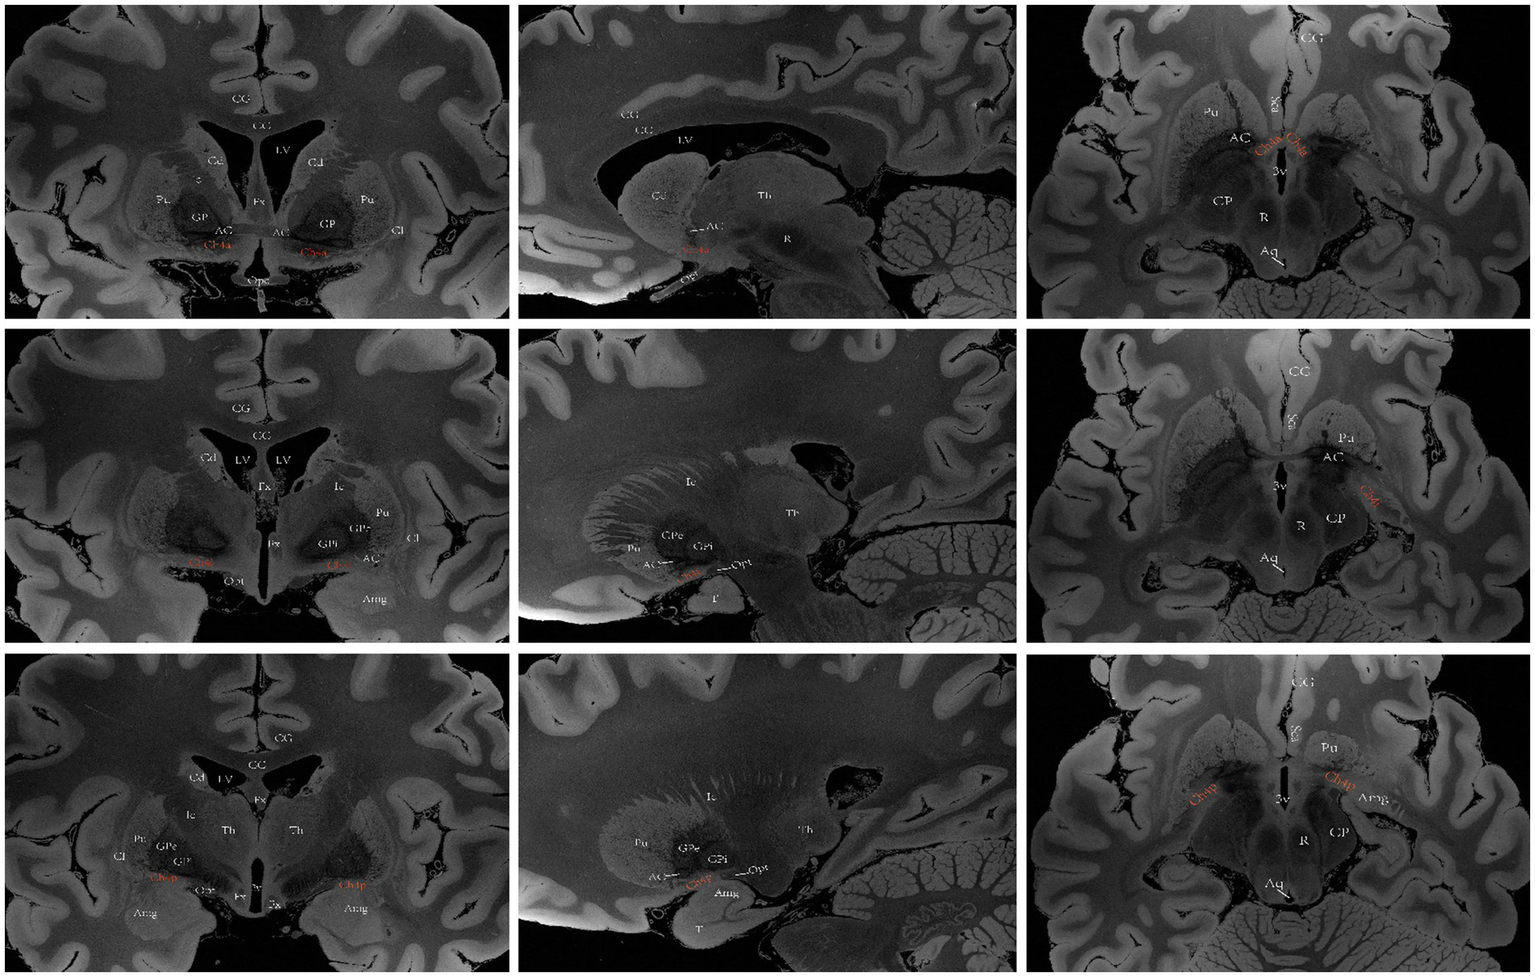

Figure 5

A diagram depicting the location of the human Ch4 on MRI. Images sourced from https://openneuro.org/datasets/ds002179/versions/1.1.0.33 (Marceglia et al., 2021). Coronal (left), sagittal (middle), axial (right). Ch4a (top), Ch4i (middle), Ch4p (bottom). LV lateral ventricle, CG cingulate gyrus, 3 V third ventricle, Fx Fornix, T temporal lobe, Th thalamus, Cd caudatum, Cl claustrum, Gp globus pallidus, GPi internal globus pallidus, GPe external globus pallidus, Pu putamen, Ic Internal capsule, Opt optic tract, Opc optic chiasma, CC corpus callosum, ScA subcallosal area, AC anterior commissure, Amg Amygdala, CP cerebral peduncle, Aq aqueduct of midbrain, R red nucleus.